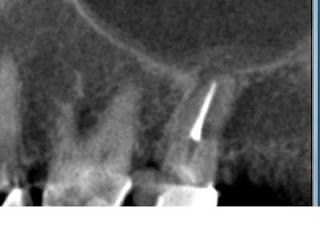

possibly apically perforated palatal obturation

This last image to the left is a horizontal slice in the apical third of the root again displaying the palatal radiolucency forming.

The CBCT shows this tooth has many problems that are not reliably correctable with endodontic retreatment. Finding the missed DB canal and even repairing the MB perforation in the furcation will not help recapture the correct path of the MB or P canals.

The CBCT confirmed with certainty what was highlighted in the periapical radiograph above. With these images, the patient was better able to visualize the root anatomy and obstacles to repairing this tooth. Consequently, the patient was much more accepting of the treatment plan of extraction.

We are increasingly using the CBCT as a diagnostic tool in our practice, specifically in complex retreatment cases or in vague diagnostic situations. In this specific case, the CBCT images confirmed suspicions about root perforations and missed anatomy. They also displayed a palatal radiolucency that was not evident on the periapical radiographs. Lastly, and not to be overlooked, the images were invaluable for patient education and treatment plan acceptance.